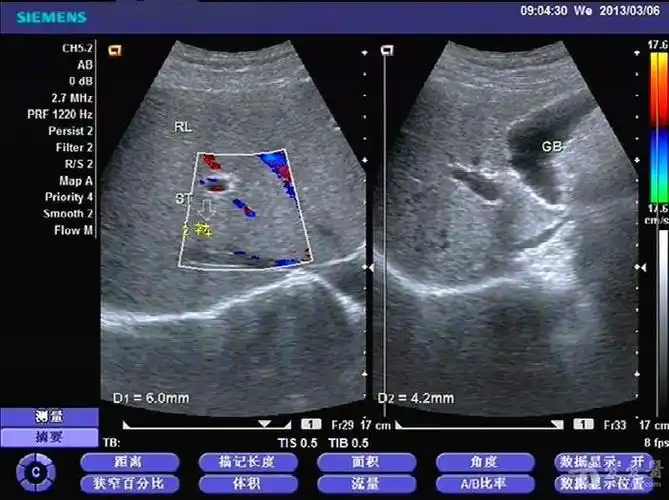

和图 声像图示胆总管(cbd)轻度扩张

门静脉轻度扩张.

见肝总管轻度扩张,通畅,左右肝管胆汁排泄良好,均无异常.